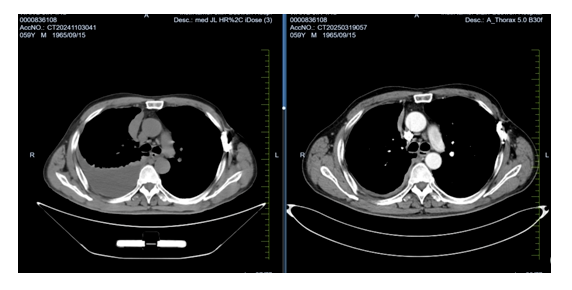

患者家住吉林省白城市鎮(zhèn)賚縣,此次因呼吸困難、胸悶來院就診。入院時患者難以平臥,進(jìn)食差,體重明顯減輕,胸部腫瘤放化療Ⅱ病區(qū)給予患者行胸部CT檢查,結(jié)果顯示:大量胸腔積液,進(jìn)一步行胸腔穿刺引流并給予完成胸膜活檢,不到一周的時間,病理結(jié)果結(jié)合免疫組化確診為“惡性胸膜間皮瘤”。這是一種較為罕見的惡性腫瘤,常與石棉暴露相關(guān),預(yù)后較差,治療難度大。

經(jīng)過系統(tǒng)治療,患者的胸腔積液明顯減少,呼吸困難顯著改善,日?;顒幽芰謴?fù),精神狀態(tài)良好。復(fù)查影像學(xué)顯示腫瘤控制穩(wěn)定,患者及其家屬對治療表示滿意。